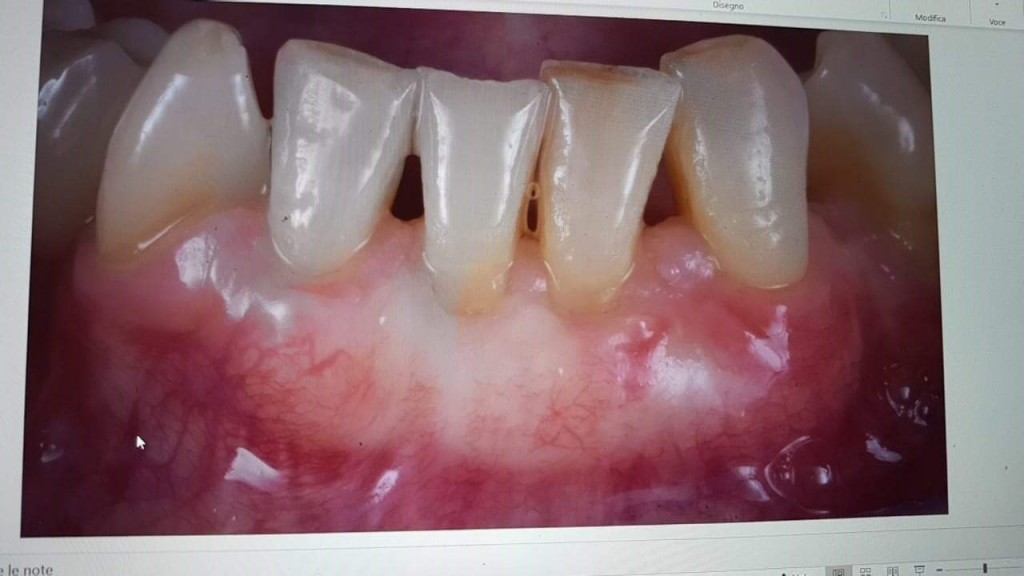

E il follow up a 2 anni che mi hanno chiesto (sorry foto dello schermo fatta con il cellulare ?)

3